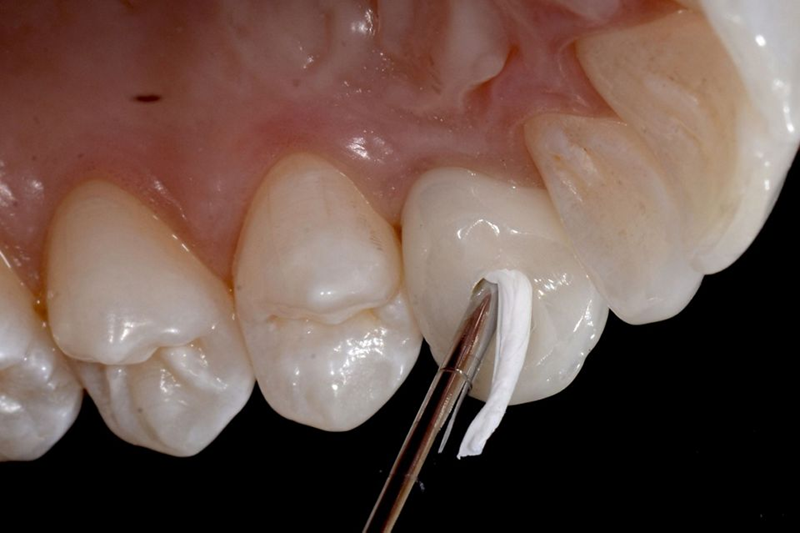

然后,使用 Virtuo Vivo™ 口内扫描仪进行数字印模,并通过此目标将专用扫描体拧在 BLX® 种植体顶部,并将牵引绳放置在牙齿 12 周围以标记线准备(图 1)。 48)。几分钟后,获得该区域的数字印模(图 49)。

Fig. 48: Final digital impression: A dedicated scan body was screwed on top of BLX implant and a retraction cord was placed around the tooth...